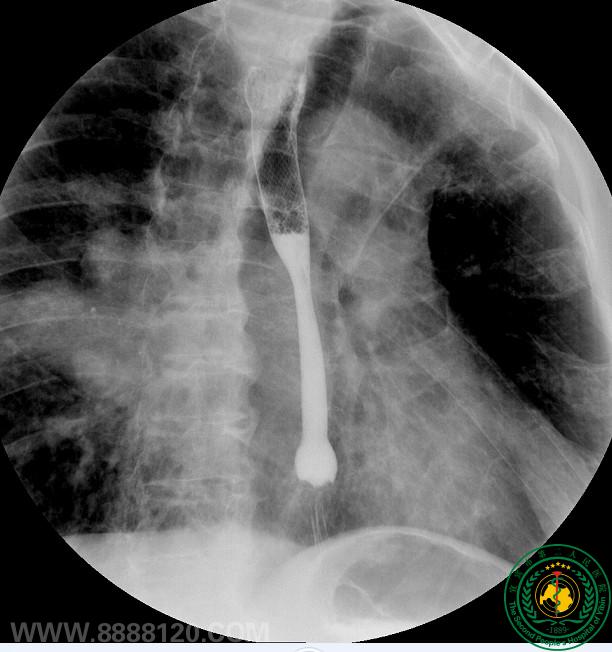

影像科介入室开展首台DSA下食道支架置入术

影像科介入室开展首台DSA下食道支架置入术1703